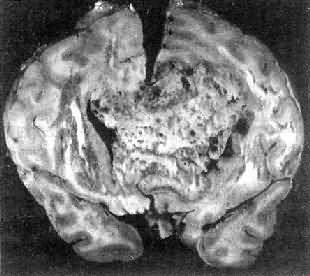

高度恶性的星形胶质细胞瘤称为多形性胶质母细胞瘤(glioblastoma multiforme),多见于成人。肿瘤好发于额叶、颞叶白质,浸润范围广,常可穿过胼胝体到对侧,呈蝴蝶状生长(图16-24)。瘤体因常有出血坏死而呈红褐色。镜下,细胞密集,异型性明显,可见怪异的单核或多核瘤巨细胞。出血坏死明显,是其区别于间变性星形胶质细胞瘤的特征。毛细血管明显增生,内皮细胞增生、肿大,可导致管腔闭塞和血栓形成。肿瘤发展迅速,预后极差,患者多在2年内死亡。

图16-24 多形性胶质母细胞瘤